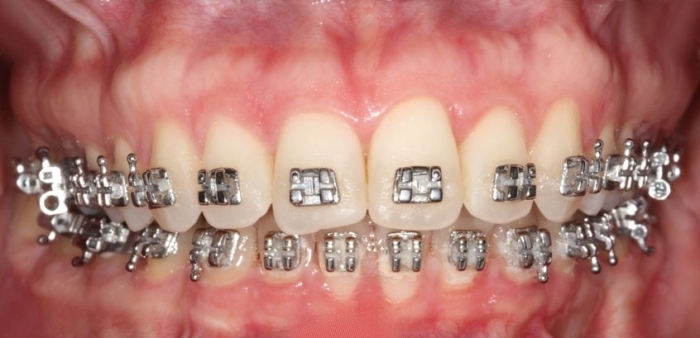

Mordida inicial

Mordida final